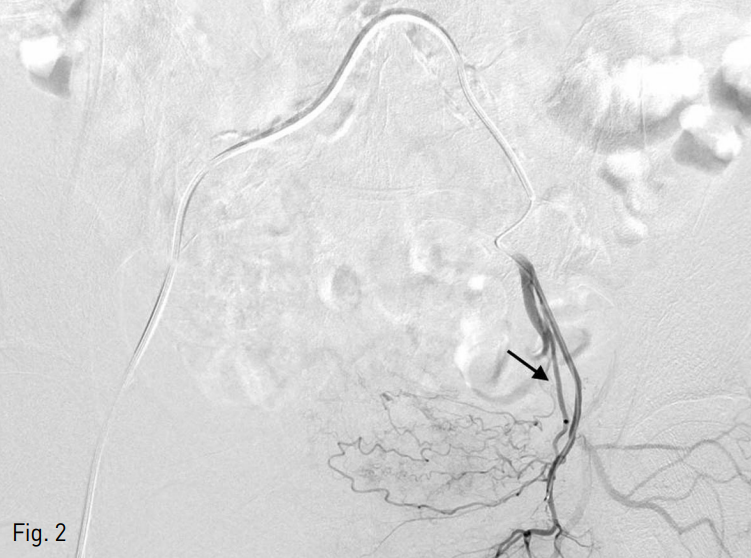

이후 경과관찰에서 혈뇨 호전되었으나 7일 후 재발하여 좌측 총대퇴동맥을 천자하여 시행한 양측 총장골동맥 및 내장골동맥 혈관조영술에서도 뚜렷한 조영제의 혈관 외 유출은 보이지 않았음. 그러나 여전히 양측 상방광동맥이 다소 발달되어 보여 gelfoam을 이용한 동일한 방법으로 색전하였음 (Fig. 3). 이후 경과관찰에서 혈뇨 보이지 않고 hemoglobin 수치 정상화되어 퇴원함.

Fig. 3

Hematuria was recurred 7 days after procedure. The selective right superior vesical angiogram shows hypervascularization without extravasation of contrast media. Both superior vesical arteries were embolized with gelfoam slurry.